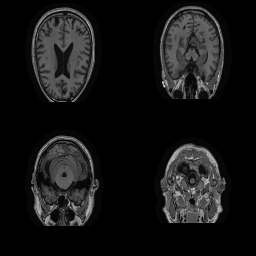

| Original | Renderings after de-identification | Original | MRI slices after de-identification | ||||||

| CP-GAN | FACE MASK | DEFACE | QUICKSHEAR | CP-GAN | FACE MASK | DEFACE | QUICKSHEAR | ||

Benchmark De-Identification Methods. We compare our result with three publicly available and widely-established methods for de-identification of MRI head scans, depicted in Figure 3. All methods have in common that they (1) are not deep-learning-driven, (2) require no additional training and (3), are used on a day-to-day basis in neuroscience and clinical research. All procedures were applied with default settings on images of resolution . The methods include QUICKSHEAR [Schimke et al.(2011)Schimke, Kuehler, and Hale], FACE MASK [Milchenko and Marcus(2013)], and DEFACE [Bischoff-Grethe et al.(2007)Bischoff-Grethe, Ozyurt, Busa, Quinn, Fennema-Notestine, Clark, Morris, Bondi, Jernigan, Dale, Brown, and Fischl]. Descriptions of the methods are provided in the Appendix. We also include MRI WATERSHED [Ségonne et al.(2004)Ségonne, Dale, Busa, Glessner, Salat, Hahn, and Fischl], a skull-stripping method that removes everything except the brain.